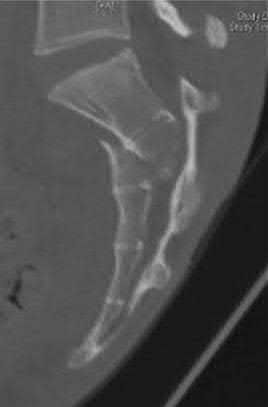

Question 20:

A 58-year-old male with long-standing, poorly controlled diabetes presents with a unilaterally swollen, warm, and erythematous foot without ulceration. Radiographs reveal osseous fragmentation, debris, and joint subluxation in the midfoot, but no significant sclerosis or osteophyte formation. According to the Eichenholtz classification of Charcot neuroarthropathy, what stage does this represent?

Correct Answer: Stage 1 (Development/Fragmentation)

Explanation:

The Eichenholtz classification describes the radiographic progression of Charcot neuroarthropathy. Stage 0 is clinically swollen and warm with normal radiographs. Stage 1 (Development/Fragmentation) features bony debris, fragmentation, joint subluxation/dislocation, and loss of joint space. Stage 2 (Coalescence) is marked by absorption of fine debris, early fusion of fragments, and sclerosis. Stage 3 (Reconstruction) shows consolidation of fractures, remodeling, and mature osteophyte formation.